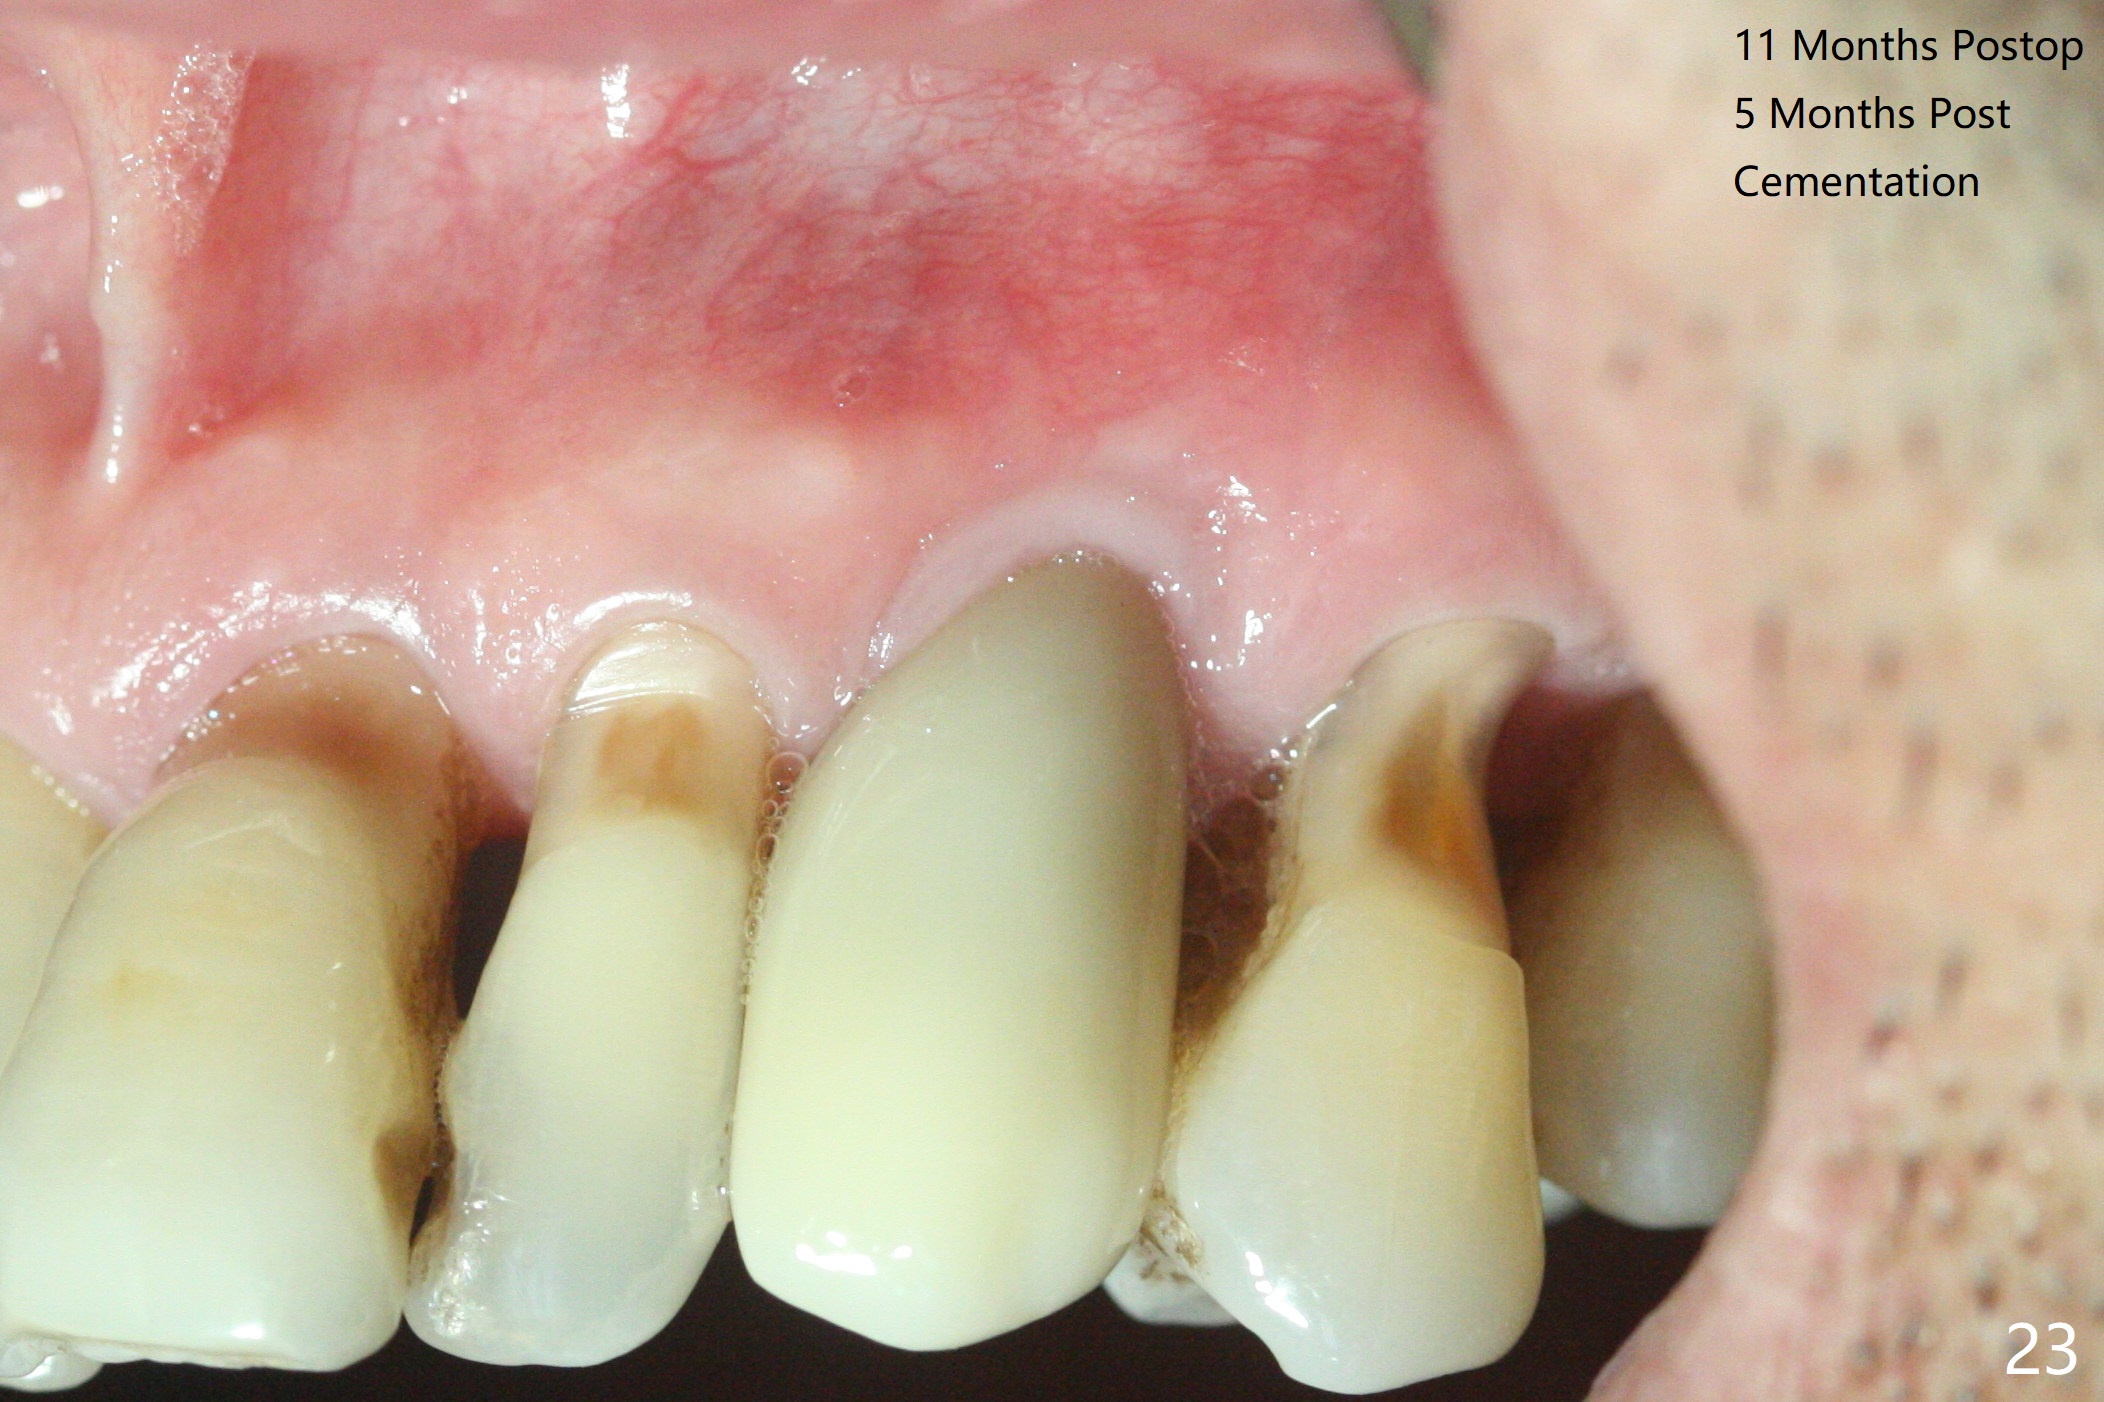

A 62-year-old man with generalized chronic periodontitis returns with chief complaint of loose tooth at #11 (Fig.1). Although a buccal fistula (Fig.1 <) is closer to #12 than to #11, percussion is more severe at #11 than 12. The buccal plate of #11 is missing, but it is possible to place a narrow immediate implant because of the wide alveolus (Fig.2). Since the gingiva is ~ 10 mm long, a mill abutment is to be used (Fig.3,5). In fact the fistula communicates with #11 extraction socket. After debridement, osteotomy is initiated (Fig.4) for a 3.8x10 mm implant ~ 35 Ncm, followed by seating a 4.5x2 mm mill abutment (Fig.5). Abundant sticky bone is placed in the remaining socket (for buccal plate reconstruction) and against the root surface of the neighboring teeth (Fig. 6 * (#10,12)). Finally 2 pieces of PRF membranes are utilized to facilitate repair of the buccal soft tissue defect (Fig.7 *). The root prominence of the canine seems to be maintained by the bone graft (Fig.8 C). Acrylic dressing holding the PRF membranes in place remains in situ with the healthy gingiva buccal (Fig.9) and palatal (Fig.10) 11 days postop. Note the acrylic locking into the undercuts of the neighboring teeth (*). 经过一段摸索发现离心每分钟1500转5分钟后,抽取上清液,接着再离心10分钟剩余上清液就形成血小板块,压制后便是血小板膜,后者似乎有助于软组织愈合,而上清液用来制备骨块,帮助硬组织生长。利用这个原则讨论以下病例治疗。The gingival margin gains ~ 5 mm 6 weeks postop when the acrylic dressing is removed (Fig.11,12 (<: previous one), as compared to Fig.7,8). 治疗结束时尖牙牙龈缘高于第一双尖牙(图七,八),六个星期后,尖牙牙龈缘却低于双尖牙(图十一,十二(箭头:原始牙龈缘))。术后2.5,4.5月基台周围牙龈似乎能与钛合金附着,防止细菌进入深部植体(图十三,十四)。临时牙冠脱落多次,可能与mill abutment太光滑有关,所以颊侧,舌侧磨成平面(图十四)。取模时好像不必取出基台清洗(仿佛没有炎症),原位用树脂延长基台。术后5个月CT显示颊侧骨板再生(图十六-十八)。取模时并没有用树脂加长基台;粘固时,牙冠颜色理想,但是照片中并不是如此(图十九,二十),颊侧骨板没有塌陷。术后11个月基台颊侧骨板没有萎缩(图二十一:B);3d图像:骨壁完全形成(图十六对比:部分形成)。密度也增高(图二十二:B),与术后五个月比较(图十七)。术后十一个月,粘固后五个月角化龈存在(图二十三),牙冠颈部有金属颜色透出,是因为二段式基台太粗了(最细4.5毫米),可以请实验室在牙冠内部涂opaque material而减轻。